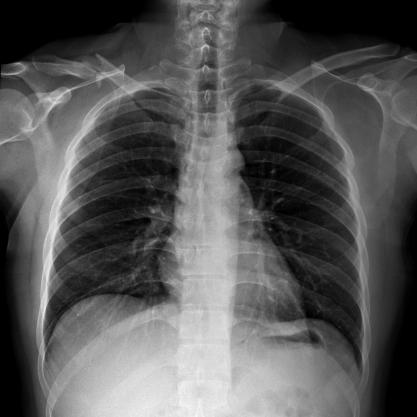

多功能動態(tài)平板DR,采用U型臂結(jié)構(gòu),具有靜態(tài)DR攝影、數(shù)字透視、數(shù)字造影和可視化攝影的功能。

滿足不同身高的受檢者快速地進(jìn)行胸片的靜態(tài)及動態(tài)檢查,適合大規(guī)模體檢。

SID可拉伸至1.8米,滿足標(biāo)準(zhǔn)胸片、職業(yè)性塵肺病檢查等特殊需求。